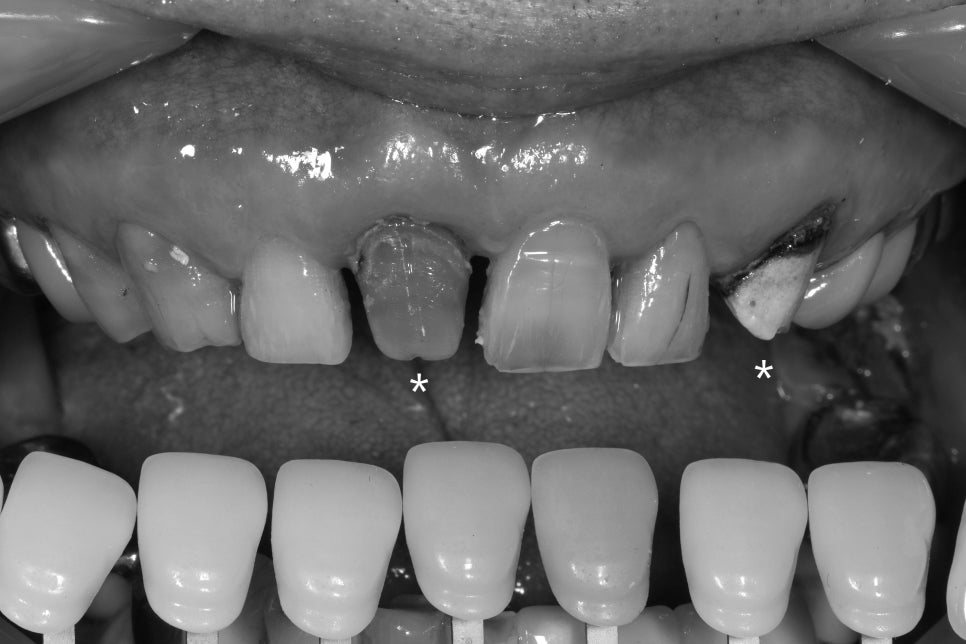

처음 오셨을 때 사진

스토리가 있는 치아를 만나니

제대로 잘 치료해드리고 싶다는 욕심이 듭니다.

예전 보철물을 벗겨내니

안쪽에 부패한 접착제와

변색된 치아가 나오는데요

별표해놓은 앞니와 송곳니를 재치료하려 합니다.

흑백으로 보니 치아의 밝기 차이가 선명하죠,

송곳니는 크라운 재료를 봐서는

씌운지 수십년이 되어보이진 않았는데

보철물 합착재가 부패, 변색된 것으로 보입니다.